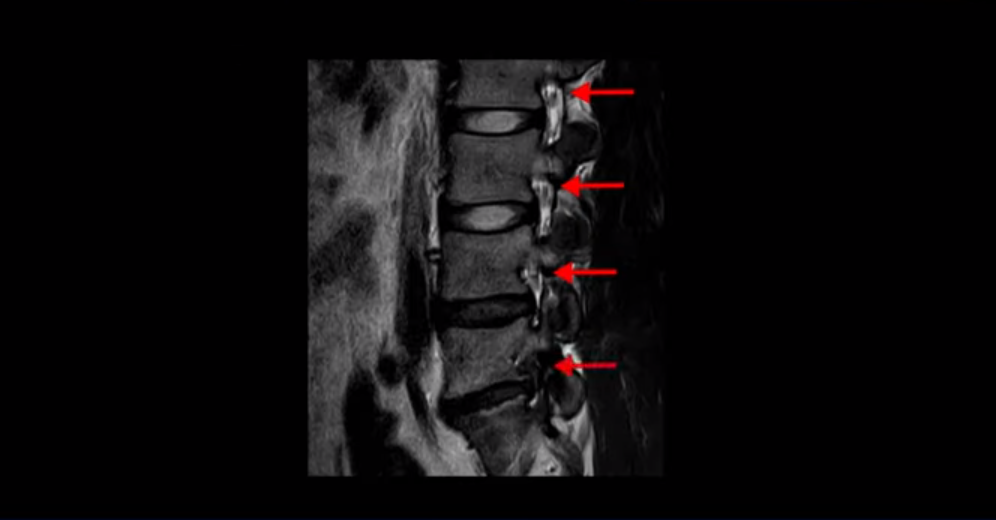

MRI를 보면 이분 5번 1번 디스크가 심하게 터져서 밀려 올라가 있습니다.

이분은 파열이 오른쪽으로 치우쳐 신경이 빠져나가는 추간공을 완전히 막고 있습니다.

다른 신경 구멍들은 열려있는데 비해 5번 1번 구멍은 까맣게 막혀있습니다.

이렇게 심하게 신경가지가 눌리니까 극심한 통증은 당연하고 발목에 마비가 생겨 힘이 빠지는 족하수 증상까지 생겼습니다.